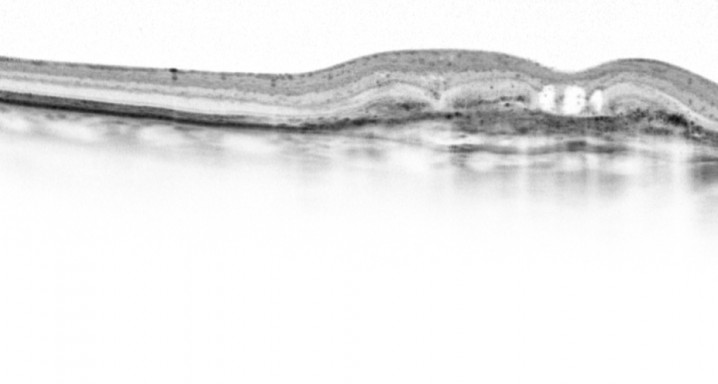

The objectives of this study are to evaluate the safety and efficacy of E10030 intravitreous injection when administered in combination with Lucentis® against a control of Lucentis® alone in subjects with subfoveal choroidal neovascularization secondary to age-related macular degeneration (AMD) in poor-responders to anti-VEGF monotherapy.

RESULTS: Patients who were previously poor-responders to Lucentis® monotherapy, after receiving the combination of Fovista (1.5 mg) and Lucentis®, gained a mean of 6.1 letters of vision on the ETDRS standardized chart at 12 weeks. Some patients showed marked lesion reduction. No significant safety issues were observed. Data under analysis pending publication.